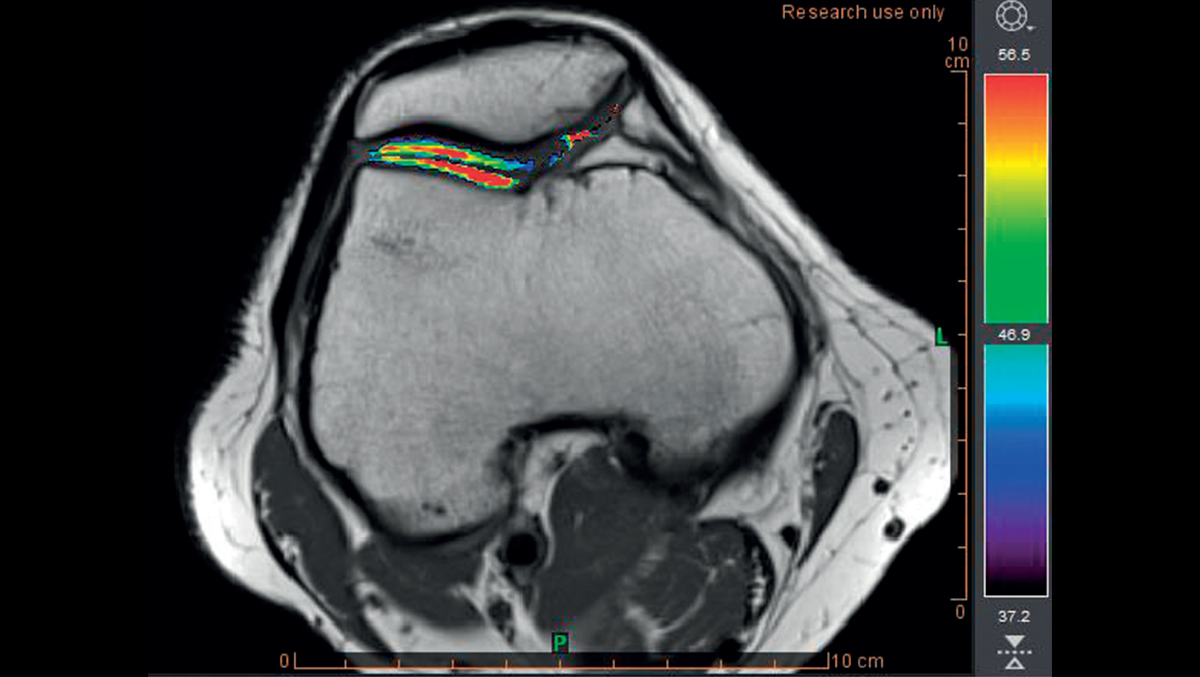

- Расчет отображения T2

- Раннее обнаружение разрушения хряща с помощью карты Thresholds T2

Обнаружение хрящевой ткани в группе риска с использованием пороговых значений времени релаксации T2